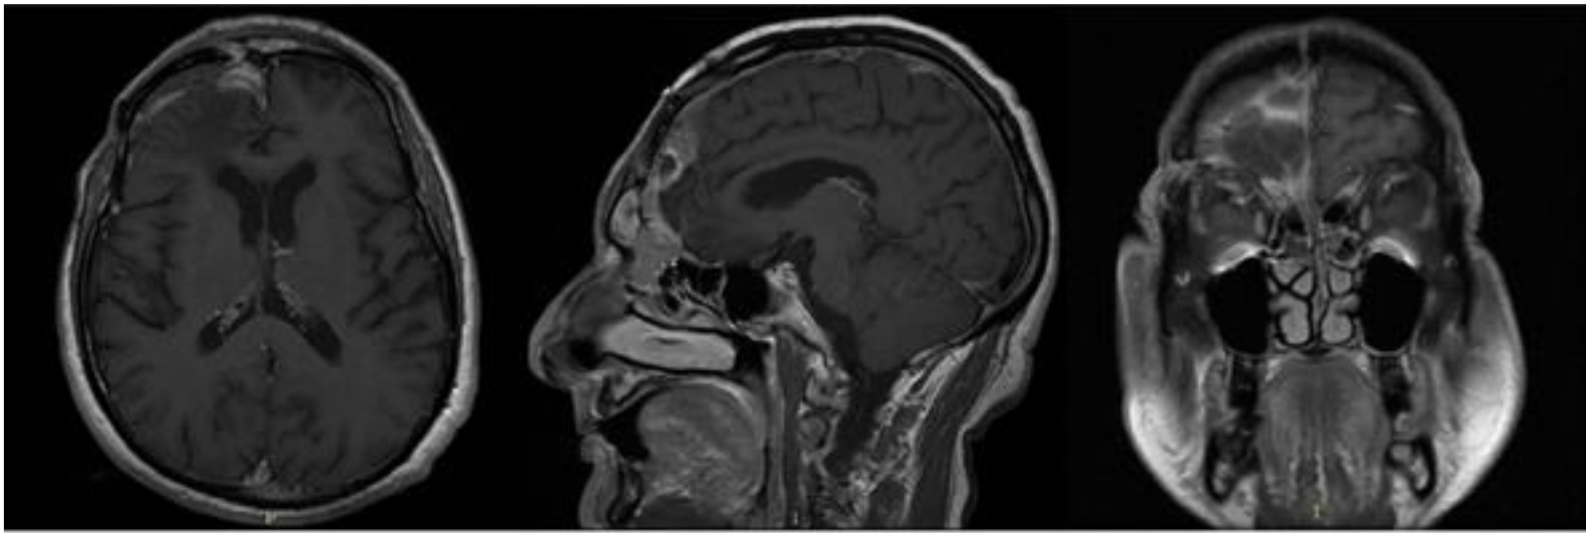

2. Case Report